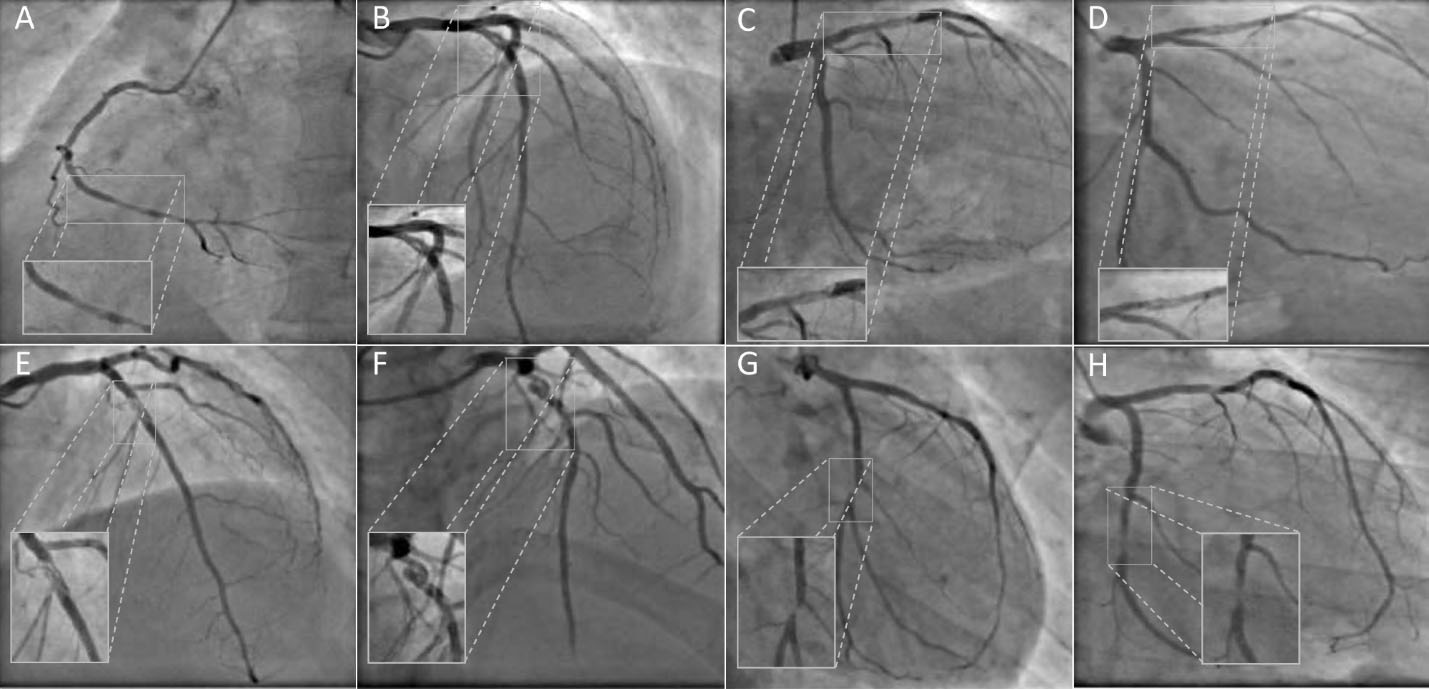

Angiographic features

The angiographic and quantitative coronary angiography (QCA) features are listed in the Table 2. The left anterior descending artery was commonly involved in five patients. Two patients had another significant ( > 50% stenosis) lesion in other artery. Patient # 8 had recanalized thrombus in the non-culprit vessel (left circumflex artery). The angiographic lesion pattern was braided (2 patients), pseudo dissection (2 patients), veiled/hazy (3 patients) and near occlusion (1 patient) as shown in . Mild degree of stenosis of ( < 50% diameter stenosis) was seen in 3 patients. All patients had TIMI 3 flow except one who had a TIMI 2 flow.

jcvtr-14-220-g001

Figure 1. Angiographic patterns of recanalized thrombus. Panel (A-H) images corresponds to the patient #1-8. Veiled appearance (A, C and H). Pseudo-dissection (B and D). Braided like (E and F). Near occlusion (G).